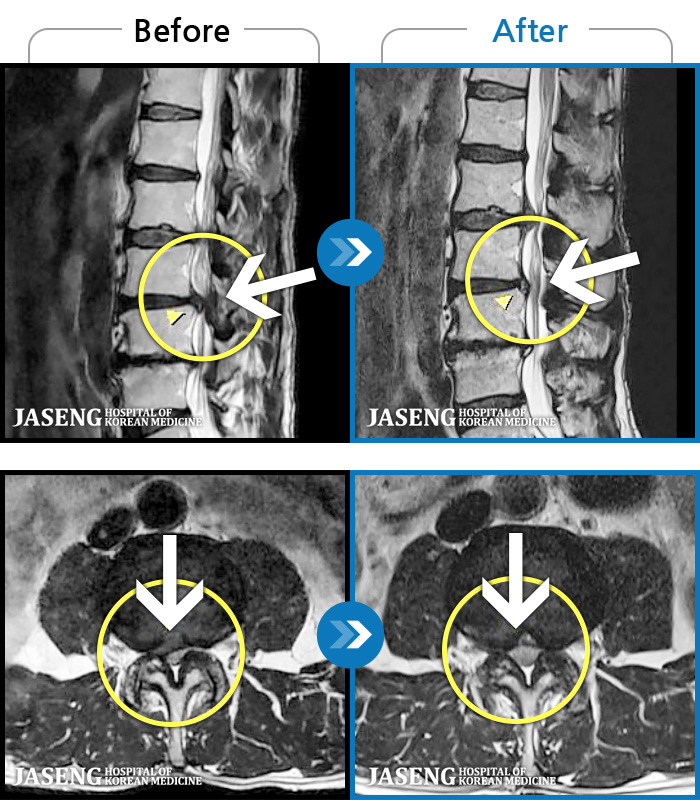

Before

After

허리 통증과 양측 둔부부터 허벅지, 발목 부위 저리는 증상으로 내원하셨습니다.

2025.05.09 ~ 2025.12.18